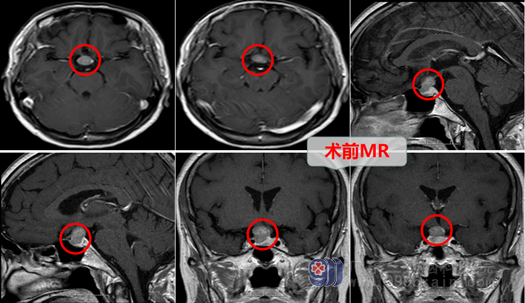

在我院查头颅MR示“鞍区占位性病变,考虑为垂体大腺瘤”。甘阿姨收治在神经外十科。外十科在欧阳辉教授的带领下,内镜微创治疗有明显的优势。经过科室讨论,甘阿姨的垂体瘤完全可以在内镜下,经鼻腔、蝶窦行微创手术。医生对甘阿姨进行了耐心的解释,使甘阿姨对垂体瘤这个病有了一定的了解,并且消除了甘阿姨对手术的恐惧,甘阿姨最终选择在外十科进行微创手术治疗。